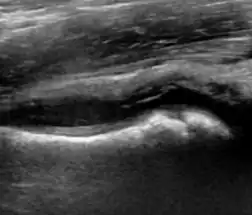

Ultrasound allows categorizing pediatric hips, according to Graf’s criteria, in four main types: normal, immature, and dysplastic (subluxed and dislocated). This classification is based on measurements of the acetabular inclination angle (alpha), cartilage roof angle (beta), and infant age. The femoral head coverage can also be determined by dividing the length of the femoral head covered by the acetabular fossa and the diameter of the femoral head. Its lower normal limits are 47% for boys and 44% for girls (Figure 11).[1]

Figure 11:

-

Useful ultrasound measures in neonatal hip sonography, alpha and beta angles.[1] -

Measurement of femoral head coverage.[1]

Ultrasound

Ultrasound is the first-choice technique for diagnosis of newborns hip dysplasia. In experienced hands with appropriate technology, ultrasound can also be useful during the first year of life. Some European healthcare systems encourage universal ultrasound screening in neonates between the sixth and eighth weeks. Although it shows higher initial costs caused, it leads to significant reduction in the total number and overall costs of dysplastic hips undergoing operative and nonoperative treatment.[1]